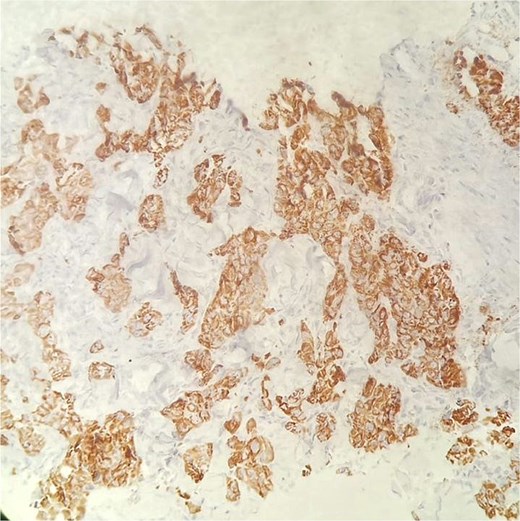

Immunohistochemical staining for HepPar-1 on the skin metastasis biopsy, showing positive cytoplasmic staining in tumor cells.

A 49-year-old male with a 20-pack-year smoking history and occasional alcohol consumption presented with a painful, nodular skin lesion on his upper back. The lesion had been present for ~1 month and had progressively increased in size. Clinically, it appeared as a solitary, firm, erythematous nodule with central ulceration and overlying necrotic crust, measuring ~1.5 × 1 cm and surrounded by a violaceous inflammatory halo (Fig. 1). A partial excisional biopsy was obtained from the center of the lesion. Histopathological examination using hematoxylin and eosin staining revealed a poorly circumscribed, infiltrating tumor within the dermis. The tumor is composed of cords and nodules of atypical cells dissecting between collagen bundles, with focal areas of gland formation. The tumor extends into the subcutaneous adipose tissue and surrounding soft tissue in an irregular infiltrative pattern. The findings confirmed invasive adenocarcinoma (Fig. 2), prompting further evaluation to assess for metastatic spread. Contrast-enhanced computed tomography (CT) of the chest, abdomen, and pelvis demonstrated a lobulated mass with heterogeneous enhancement centered at the left pulmonary hilum, invading adjacent bronchi and vascular structures (Fig. 3A). Multiple hypodense lesions in the liver were consistent with hepatic metastases (Fig. 3B). Additionally, numerous lytic bone lesions were noted involving the ribs, vertebral bodies, sternum, and right pubic bone, indicating widespread skeletal metastases.A positron emission tomography–computed tomography (PET-CT) scan was not performed due to lack of availability in Syria. Bronchoscopy revealed complete obstruction of the left upper lobe bronchus, and a biopsy was obtained from the lesion. Histopathological examination demonstrated features consistent with invasive high-grade HAC, characterized by large polygonal cells with abundant eosinophilic cytoplasm and prominent nucleoli, resembling HCC morphology (Fig. 4). To further support the diagnosis, immunohistochemical staining was performed. The tumour cells showed strong positivity for CK7, HepPar-1, and CK19 (Fig. 5), and were negative for TTF-1, Napsin-A, p40, alpha-fetoprotein (AFP), and Glypican-3. Serum AFP level was within normal limits. This immunoprofile supports the diagnosis of HAC of pulmonary origin. In addition, immunohistochemical staining for HepPar-1 was performed on the biopsy from the subcutaneous metastasis, which also showed positive staining (Fig. 6). This finding further supports the lung as the primary site of the hepatoid carcinoma, given the matching immunophenotype between the primary lung tumour and the cutaneous metastasis.

Distinguishing HAL from metastatic HCC remains a significant diagnostic challenge. In this case, immunohistochemistry played a crucial role; the tumor cells were positive for CK7, Hep-Par1, and CK19, and negative for TTF-1, Napsin-A, p40, AFP, and Glypican-3. This immunoprofile supports a primary pulmonary origin and helps exclude metastatic HCC.